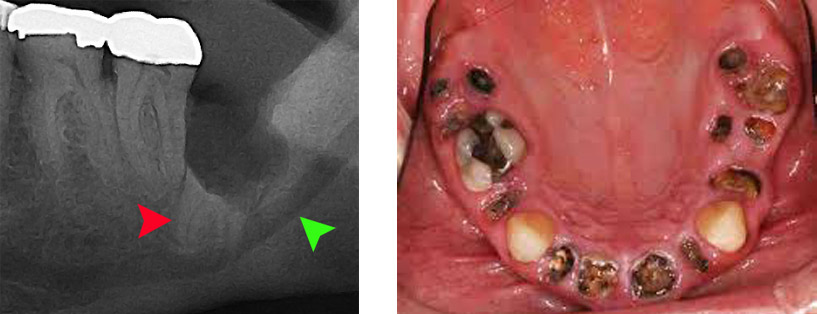

Υπάρχουν περιστατικά με επιπλέον του φυσιολογικού αριθμού δόντια στην άνω ή στην κάτω γνάθο. Τα υπεράριθμα δόντια μπορεί να είναι ασυμπτωματικά, μπορεί όμως να δημιουργούν προβλήματα όπως η παρεμπόδιση της ανατολής παρακείμενων δοντιών ή η πρόκληση επώδυνων συμπτωμάτων λόγω της πίεσης που ασκούν στα γειτονικά ανατομικά μόρια. Μετά από σωστή κλινική και απαραιτήτως ακτινογραφική μελέτη με τομογραφία κωνικής δέσμης (CBCT SCAN) προσδιορίζεται η θέση του υπεράριθμου δοντιού καθώς και ο ορθότερος τρόπος χειρουργικής προσπέλασης.

Στα οστά της άνω και κάτω γνάθου συχνά δημιουργούνται κοιλότητες που περιβάλλονται από μία μεμβράνη και περιέχουν υγρό, είναι απολύτως καλοήθεις και δημιουργούνται αυτόματα ή από νεκρά δόντια. Η χειρουργική αφαίρεση σε περιοχές με αυξημένο πάχος του εξωτερικού φλοιού του οστού μπορεί να απαιτήσει εκτεταμένη αφαίρεση αυτού και πιο σύνθετες μορφές αποκατάστασης.

Κατά τη διάρκεια μίας εξαγωγής υπάρχει περίπτωση να σπάσει ένα κομμάτι της ρίζας του δοντιού μέσα στο φατνίο. Προκειμένου να αφαιρεθεί αυτό το υπόλειμμα, άλλοτε αρκεί μία αντιμετώπιση με απλούς χειρισμούς και άλλοτε χρειάζεται η συνδρομή της χειρουργικής. Η χειρουργική επίσης συμβάλλει στην ταχεία απομάκρυνση υπολειμμάτων ριζών σε περίπτωση όπου ένα δόντι έχει τερηδονιστεί σε τέτοιο βαθμό με αποτέλεσμα να έχουν απομείνει μόνο οι κατεστραμμένες ρίζες.